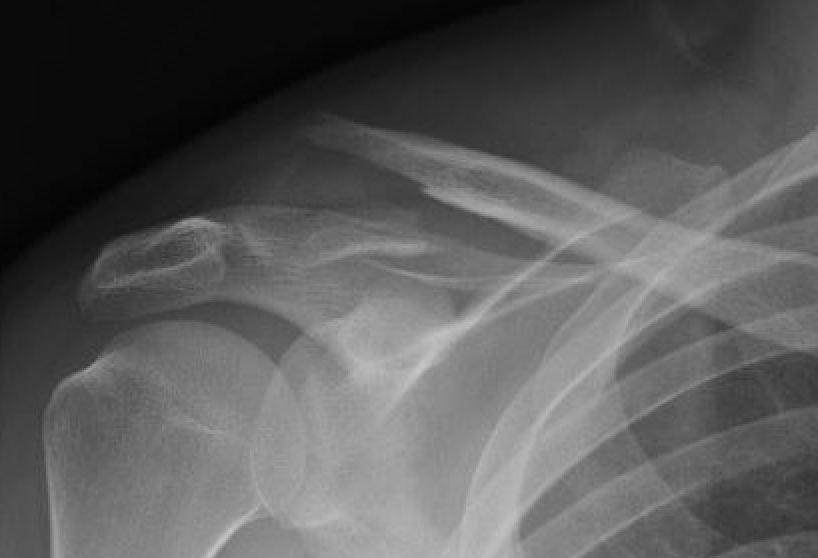

Neer Classification

Fracture lateral to the CC ligaments Non displaced

Fracture medial to the CC ligaments CCL ligaments attached to lateral fragment Medial fragment displaced superiorly |

Between conoid and trapezoid Conoid disrupted Trapezoid remains attached to the lateral fragment |

Lateral to CC ligaments Intra-articular extension Stable |

Periosteal sleeve disruption Pediatric Medial fragment displaced |

Comminuted Type II Medial fragment displaced |

Type I

Type II

Type V